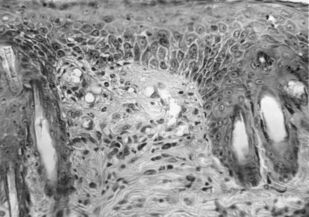

Лишай Видаля: экспериментальное и клиническое применение ультрафонофореза флюоцинолона ацетонида

Монография предназначена для врачей дерматовенерологов, физиотерапевтов, врачей общей практики, студентов выших медВУЗОВ для эффективного и обоснованного применения метода ультрафонофореза флюоцинолона ацетонида у пациентов с простым хроническим лишаем (лишаем Видаля, ограниченного или очагового нейродермита).